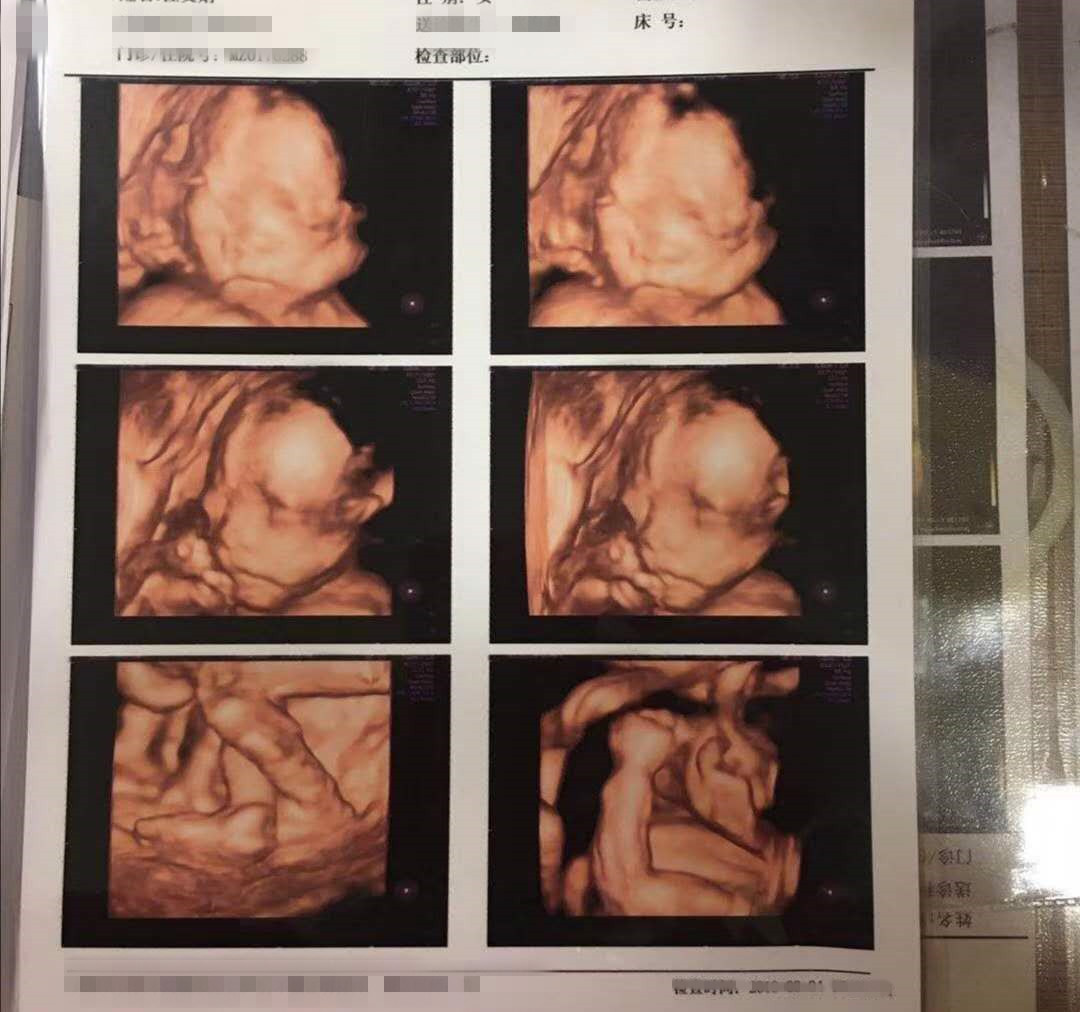

还有几个月我们就要和两个小天使见面了,上个月照过了思维彩超,透着小小的显示屏看到两个小宝宝皱皱巴巴地蜷缩在一块儿,感慨生命真的很奇妙。在这一片岁月静好的背后,确实一段七年不孕的辛酸往事。

如今,已经安全度过四维了,七年的不放弃终于换来了一个圆满的结果,我们已经给即将诞生的两个小天使准备好了一切行头,让他们知道爸爸妈妈有多么殷切地期待他们的到来。希望大家都能圆梦,等待有所值!